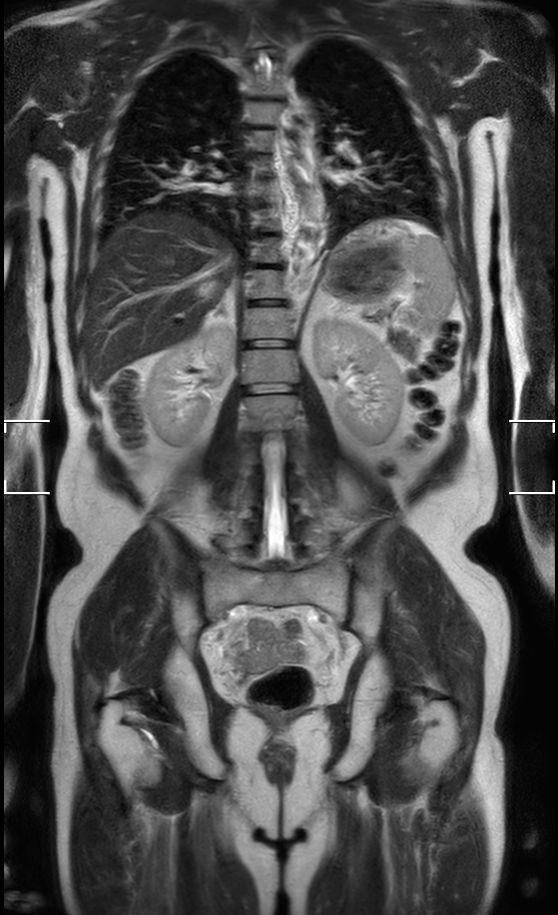

Coronal T2w TSE (2 stations)Dual coil

Coronal T2w TSE (1 station)Chest Abdomen - Single coil

Coronal T2w TSE (1 station)Abdomen Pelvis - Single coil